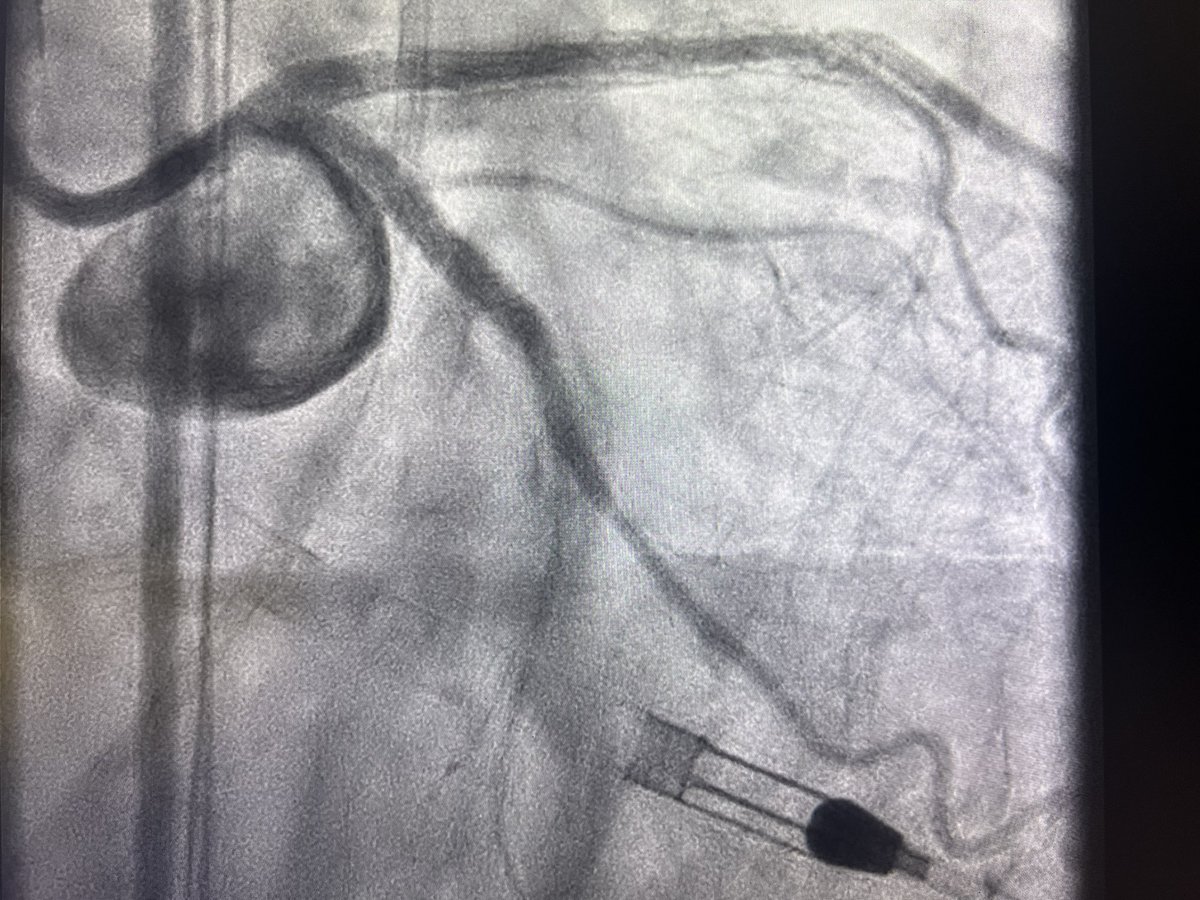

Great cases today for an advanced operators course. PercAx LM DK crush case followed by Impella assisted IVL bifurcation LM case. We needed the help of our guest colleagues for these cases. Thanks New Cardiovascular Horizons for the live case opportunity. Big props to St Johns cath lab staff!

Great cases today for an advanced operators course.  PercAx LM DK crush case followed by Impella assisted IVL bifurcation LM case.  We needed the help of our guest colleagues for these cases. Thanks <a href="/NCVHonline/">New Cardiovascular Horizons</a> for the live case opportunity. Big props to St Johns cath lab staff!